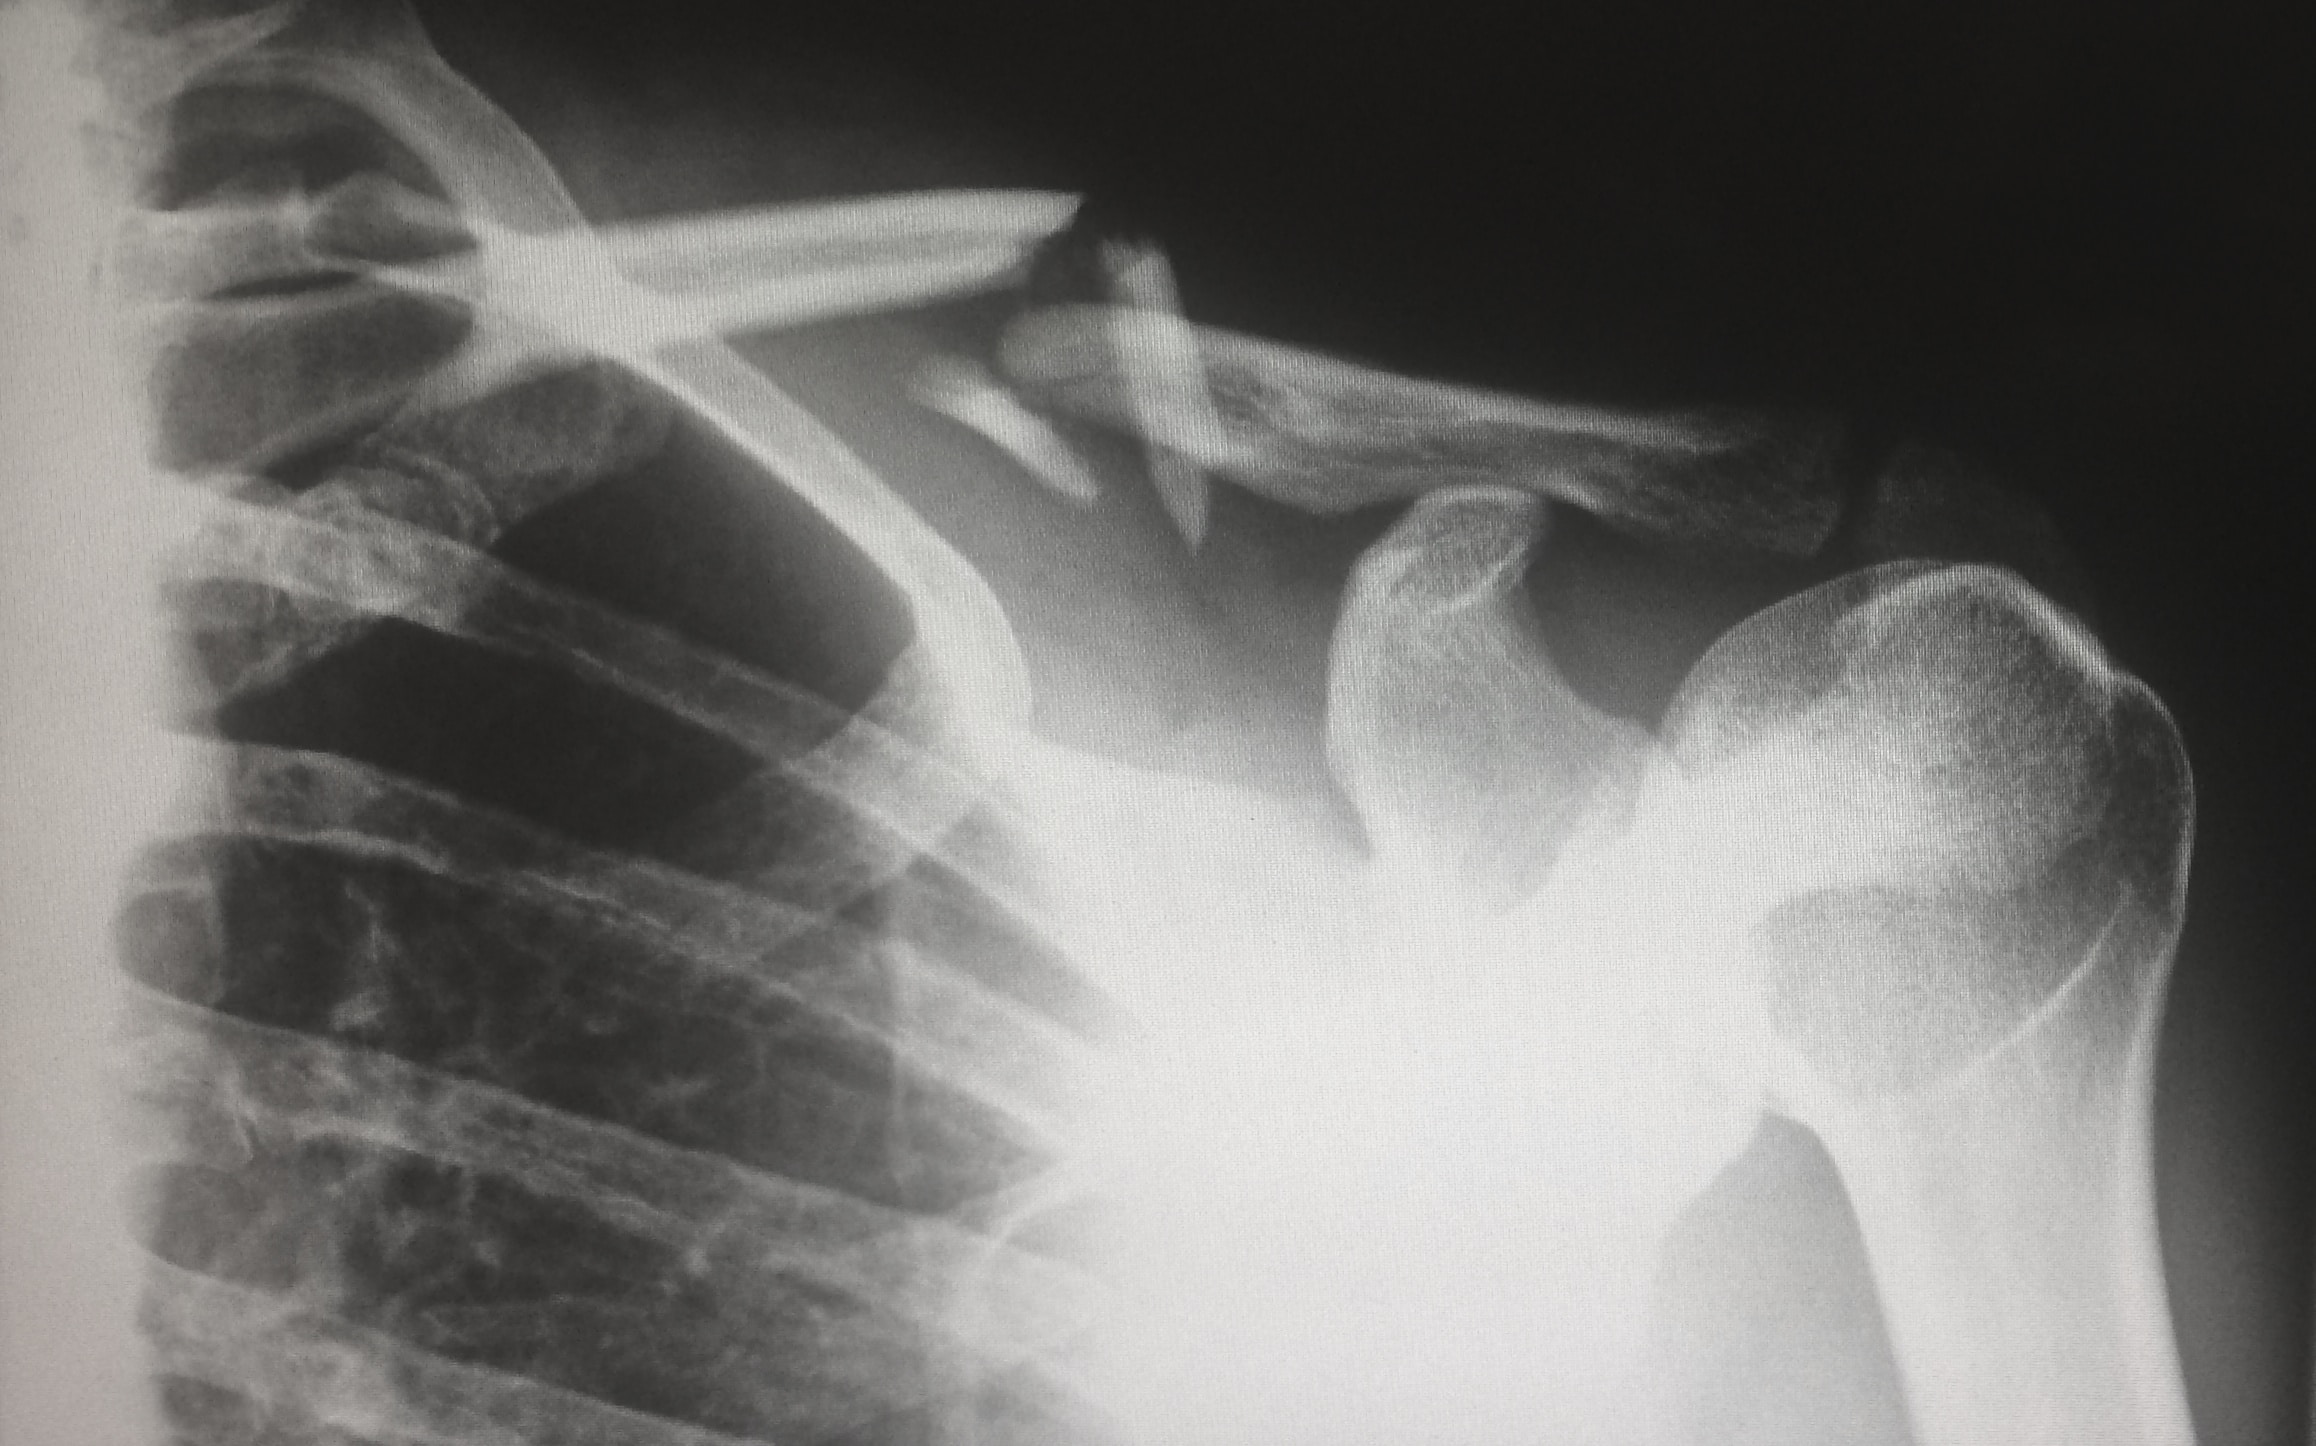

뼈는 우리 몸의 구조적인 요소 중 하나이며, 우리가 건강하고 활동적인 삶을 유지하는 데 필수적입니다.

뼈 잘 붙는 음식을 먹으면 뼈 건강을 지키는 데 매우 중요한 영양소를 섭취할 수 있습니다.

이번에는 뼈 잘 붙는 음식과 빠른 회복 방법에 대해 알아보겠습니다.